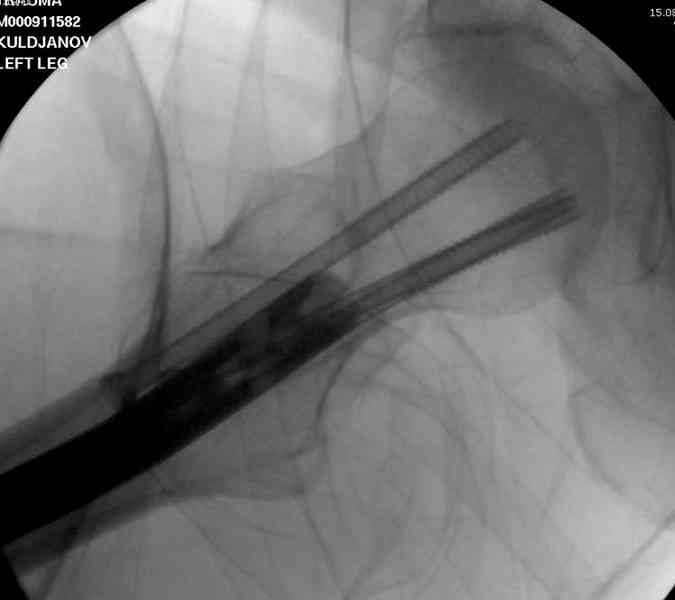

На второй день (7) обнаружен пропущенный перелом,

и проведены шурурпы через и спереди штифта без удаления.

Послеоперационные снимки